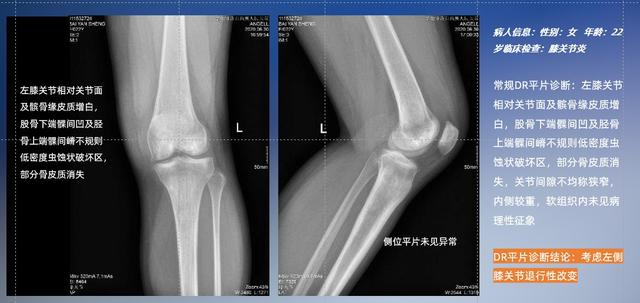

普通平片扫描与WR-3D扫描前后诊断结果对比

与此同时,数字化X线摄影技术相较于CTMRI来说,能快速获取真实、直观、满足临床需要的影像。DR的图像具有图像层次丰富、空间分辨力高、影像边缘锐利清晰、密度分辨力高级细微结构表现出色等特点,针对膝关节解剖结构数字化X线摄影技术应用价值很高,尤其是是对骨小梁与骨皮质的显示非常清楚。在负重位状态下,数字化X线三维摄影扫描与重建,能够更好的呈现受检者关节受力改变的状态。广东会科技创新的WR-3D动态三维数字化X线摄影技术,通过数字化X线摄影完成三维扫描并重建三维影像信息,包括MPR多平面重建、MIP重建以及VR绘制。扫描时间短,剂量相较于CT设备大幅缩减,同时成本更低,在临床诊断以及医疗方案制定中具有极大的价值意义。相较于普通平片下的负重位扫描,负重位动态三维扫描摄影技术能够避免二维状态下的组织结构重叠、密度分辨率不足、组织解剖结构难以分辨等问题,WR-3D支持多角度的动态三维摄影观察,能全面的呈现被检查部位在多个角度下三维影像信息,极大的减少了二维负重位检查的漏诊率。